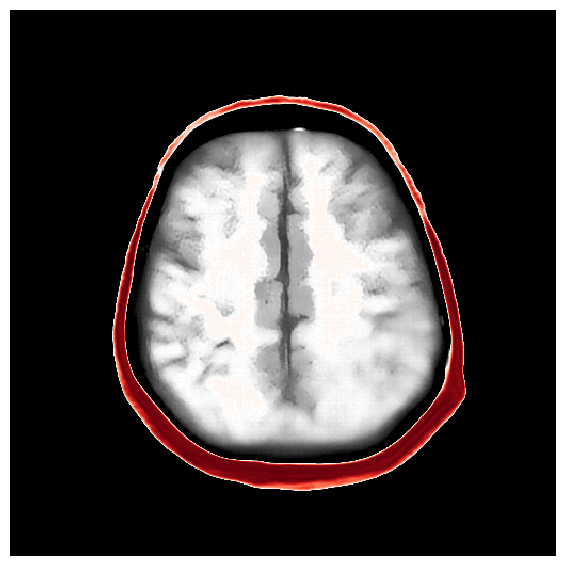

4.2.1 Brain prior samples:

The first step of implementing ASPIRE concerns obtaining samples from a realistic prior for the target parameter vector , in this case, gridded velocity parameters of human brains and skulls. The parameters collected in the MIDA dataset [56] correspond to a single 3D volume for the acoustic velocity collected from a single subject and will unfortunately not be appropriate to train a neural model that will generalize to other human patients. As far as we know, there is no dataset that includes acoustic velocity collected from many patients, so we made our own dataset based off the multi-subject FASTMRI dataset [57]. This custom dataset, detailed in Section \thechapter.A, comprises N=1000 diverse acoustic velocity parameters collected from different human patients, . This size of datasets facilitates generalization of the amortized posterior sampler across different datasets collected from unseen patients. The dataset is accessible via the repo ASPIRE.jl.

Appendix \thechapter.A FASTMRI acoustic dataset creation

Based off of the MRI dataset [57], we manually assigned acoustic values to MRI intensities by following the table of acoustic brain tissue properties in the supplemental section of [47]. Although MRI intensities are not necessarily related to acoustic tissue properties, we found that we could produce reasonably realistic acoustic parameters as compared to the acoustic parameters from the MIDA volume. In Figure 19, we show some example training acoustic parameters. We also plot the average and standard variation between all 1000 training samples in Figure 20. From these plots, we note that there are few similarities between training examples apart from the biologically consistent human brain structures.